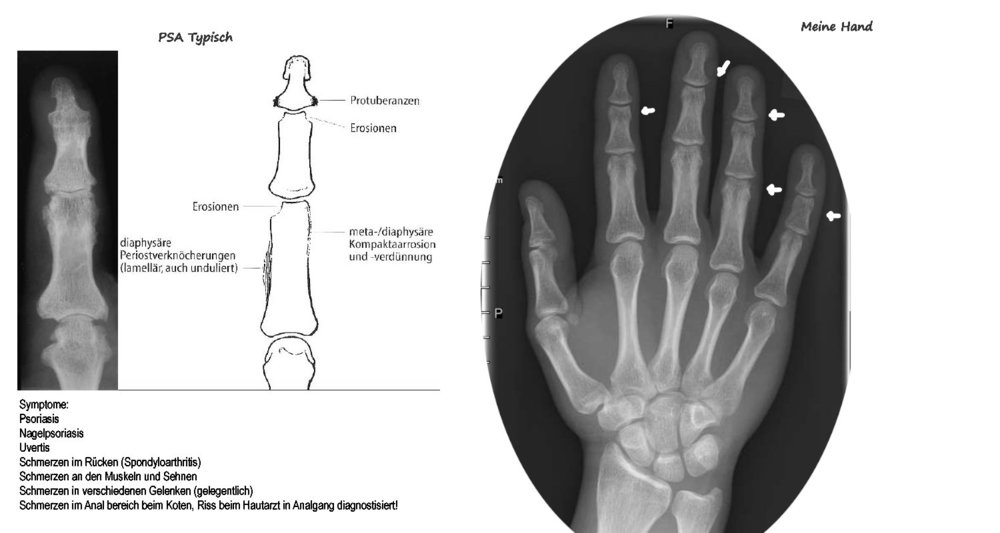

PSA? Wer kennt sich aus?